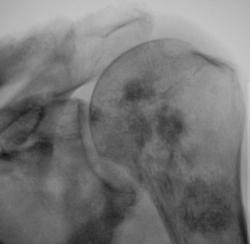

Метастаз в головку и шейку бедренной кости.

Наблюдения Виктора Григоревича.

Вот еще метастазы в кости, вот только точно не помню откуда.

Наблюдение Виталия Валерьевича.